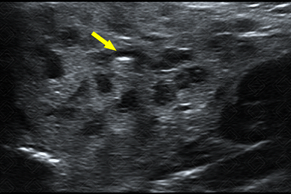

Descrição das figuras: Pré-escolar, 4 anos, com relato materno de abaulamento na face direita e febre. Mãe refere outros episódios prévios. Realizada ultrassonografia cervical que evidenciou aumento da glândula parótida direita, com textura heterogênea e áreas hipoecoicas, com focos hiperecogênicos puntiformes no seu interior (setas amarelas). Correlacionando história clínica e achados de imagem, devemos pensar em parotidite recorrente da infância. [cms-watermark]

• O exame de imagem de escolha , por se tratar de paciente pediátrico, é a ultrassonografia cervical por que favorece a boa avaliação das glândulas salivares, inclusive da parótida. Nela observaremos a glândula com dimensões aumentadas, heterogênea, com áreas hipoecoicas de permeio, contendo focos ecogênicos puntiformes no seu interior, correspondendo aos ductos ectasiados. Observam-se, ainda, linfonodos intra-parotídeos (figuras acima) ;